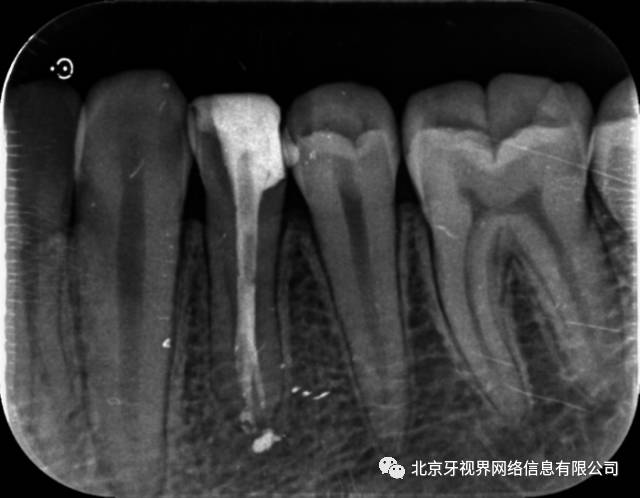

根管大赛参赛病例——左下第一前磨牙根尖分叉一例 作者:屈博

研究者们指出,大多数牙齿都有数个根尖孔,根管内有鳍状突起,三角形物